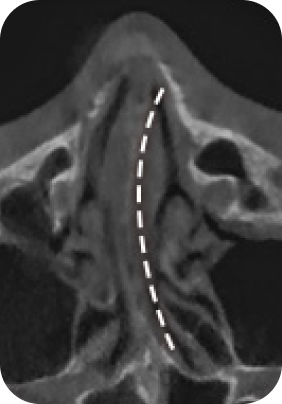

맘모톰, 비후성/알레르기 비염, 비중격 만곡증, 비밸브 협착증 등

질환에 따라 3DCT, 내시경 검사, 고해상도 초음파를 통해 정밀진단 후

정확한 증상에 따라 보험 실비 청구가 가능합니다.

대학병원급 검사 장비

유방외과 전문의 / 이비인후과 전문의

디에이성형외과에서는 대학병원급 검사 장비 시스템

각 분과의 전문의와 성형외과 전문의가 협진하여